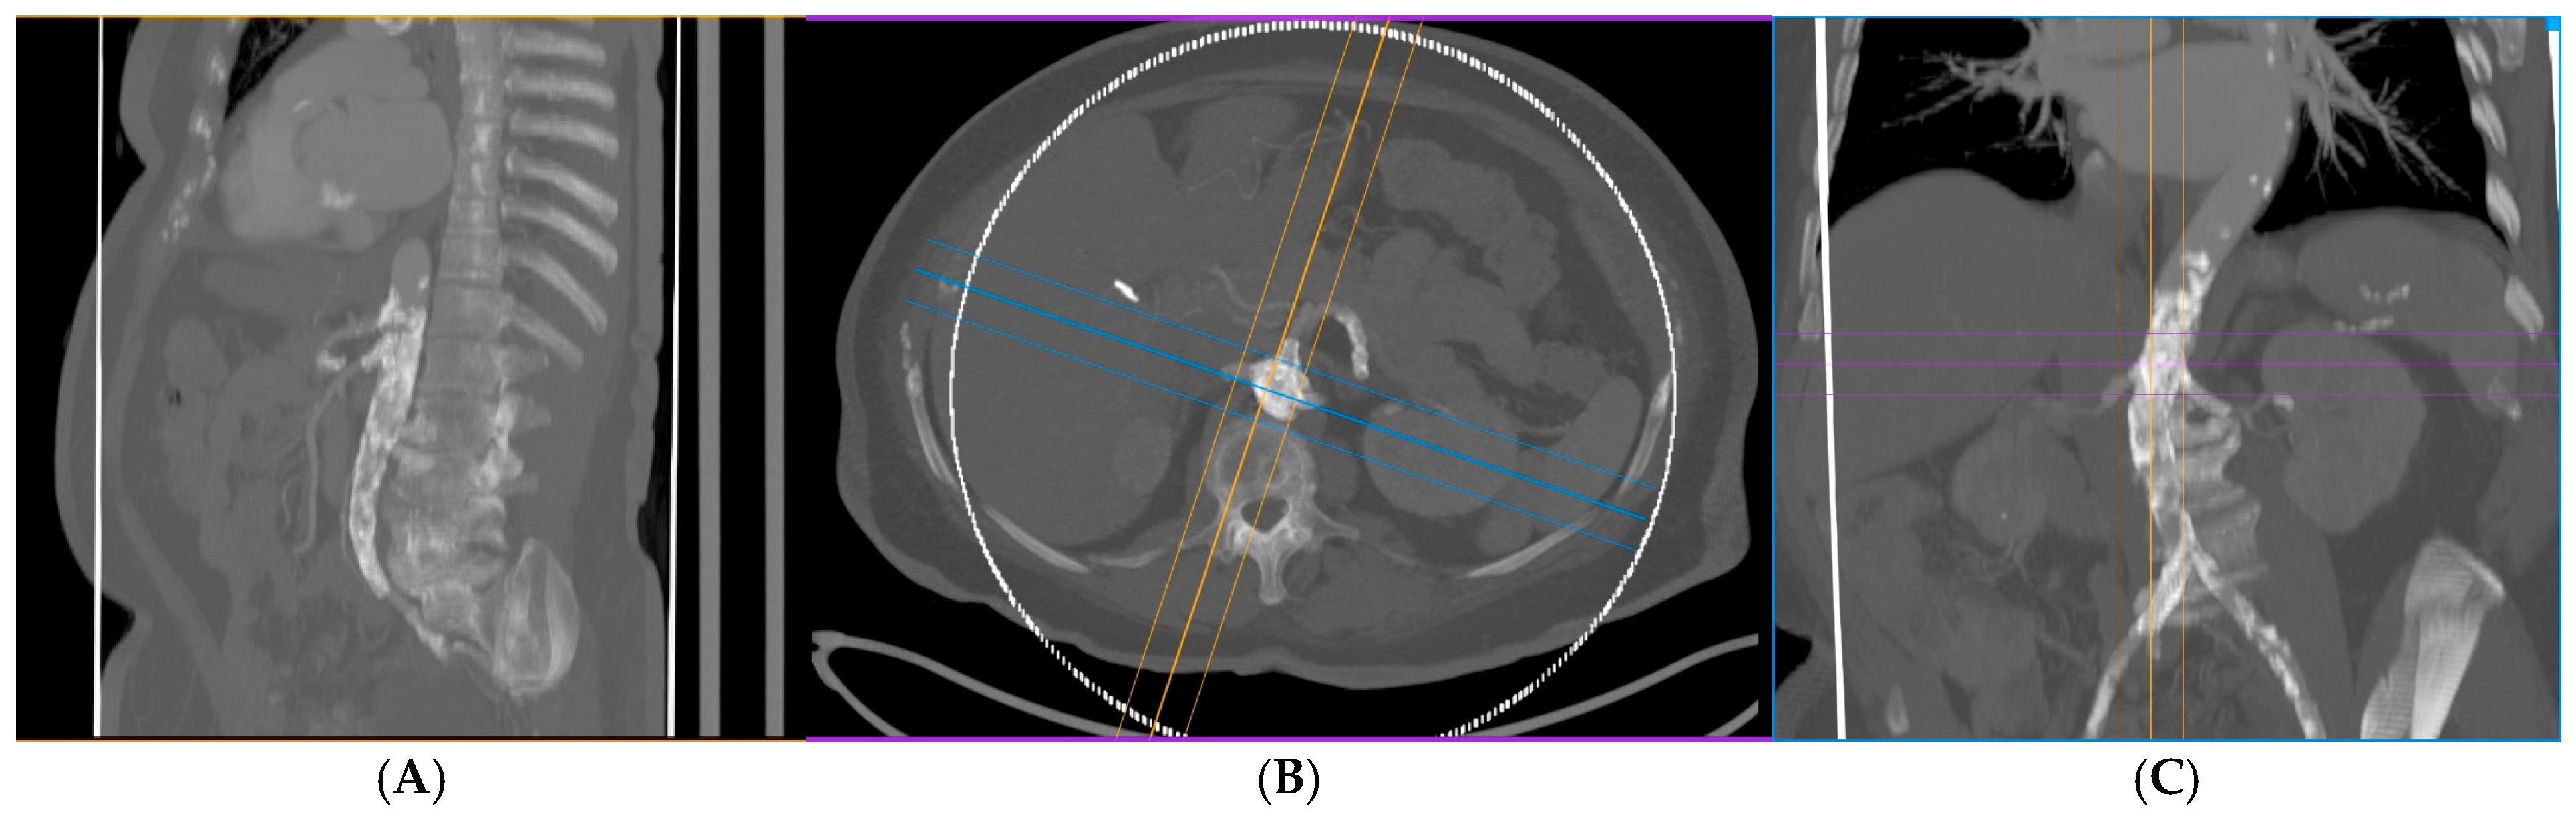

2.2. Preoperative Evaluation

2.3. Endovascular Procedure